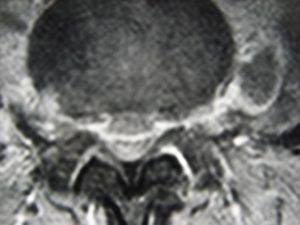

Εικόνα 2 (α,β,γ,δ,ε,ζ)

Μαγνητική Τομογραφία-Ακολουθία Τ1 και Τ2 της Ο.Μ.Σ.Σ. γενόμενη προ της εισαγωγής του στις 04/06/2007.

Οβελιαία τομή (α,β). Καταδεικνύεται η εκφύλιση του μεσοσπονδύλιου δίσκου στα επίπεδα Ο3-Ο4, Ο4-Ο5 και Ο5-Ι1 με μικρή οπίσθια προβολή ιδιαίτερα στο επίπεδο Ο3-Ο4. Ωστόσο στο επίπεδο αυτό είναι εμφανής η πρόσθια αποστηματική συλλογή.

Μετωπιαία τομή (γ,δ) Δεν είναι εμφανής η ύπαρξη της αποστηματικής συλλογής ωστόσο στο επίπεδο Ο3-Ο4 (Α) πιθανολογείται η ύπαρξη μάζας η οποία προκαλεί απώθηση του υοϊτού μυός.

Εγκάρσια τομή (ε,ζ) Είναι σαφής η ύπαρξη προ και παρασπονδυλικής αποστηματικής συλλογής και σε μικρότερο βαθμό οπισθίως εντός του σπονδυλικού σωλήνα.